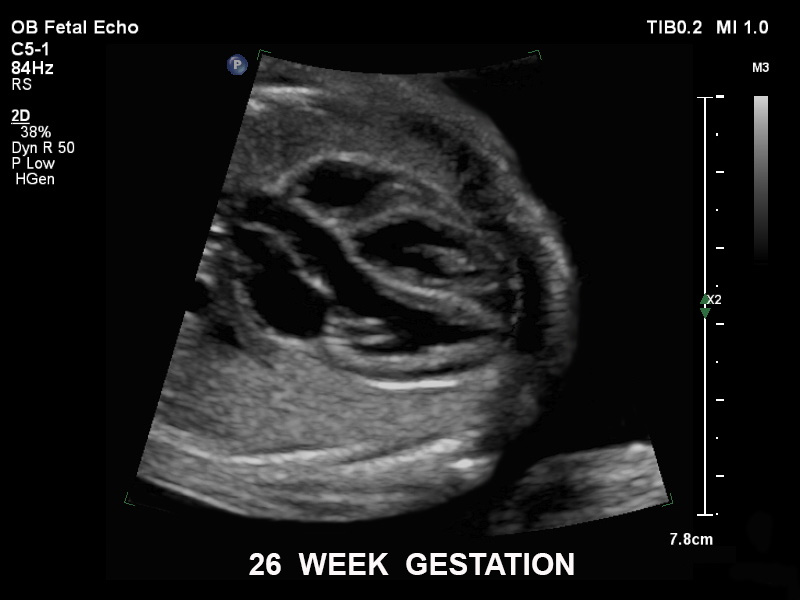

• C5-1 PureWave-Breitband-Convex-Schallkopf für hohe Eindringtiefen in der Gynäkologie und der Geburtshilfe, für Patientinnen mit Schwangerschaftsdiabetes oder vorzeitigem Blasensprung